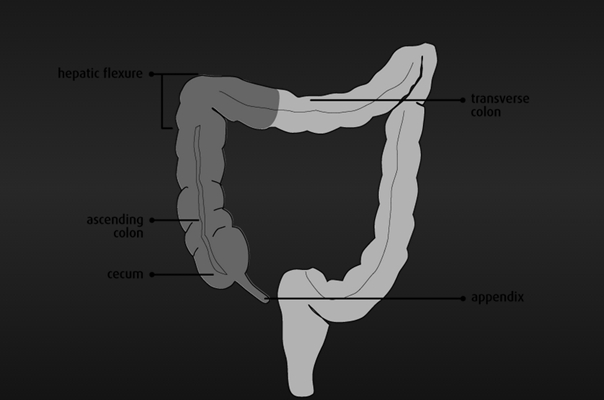

盲腸的位置 (50)

盲腸的位置 (6)

盲腸的位置 (7)

盲腸的位置 (8)

盲腸的位置 (9)

盲腸的位置 (46)

盲腸的位置 (47)

盲腸的位置 (48)

盲腸的位置 (49)

盲腸的位置 (5)

盲腸的位置 (42)

盲腸的位置 (43)

盲腸的位置 (44)

盲腸的位置 (45)

盲腸的位置 (41)

盲腸的位置 (40)

盲腸的位置 (30)

盲腸的位置 (31)

盲腸的位置 (32)

盲腸的位置 (33)